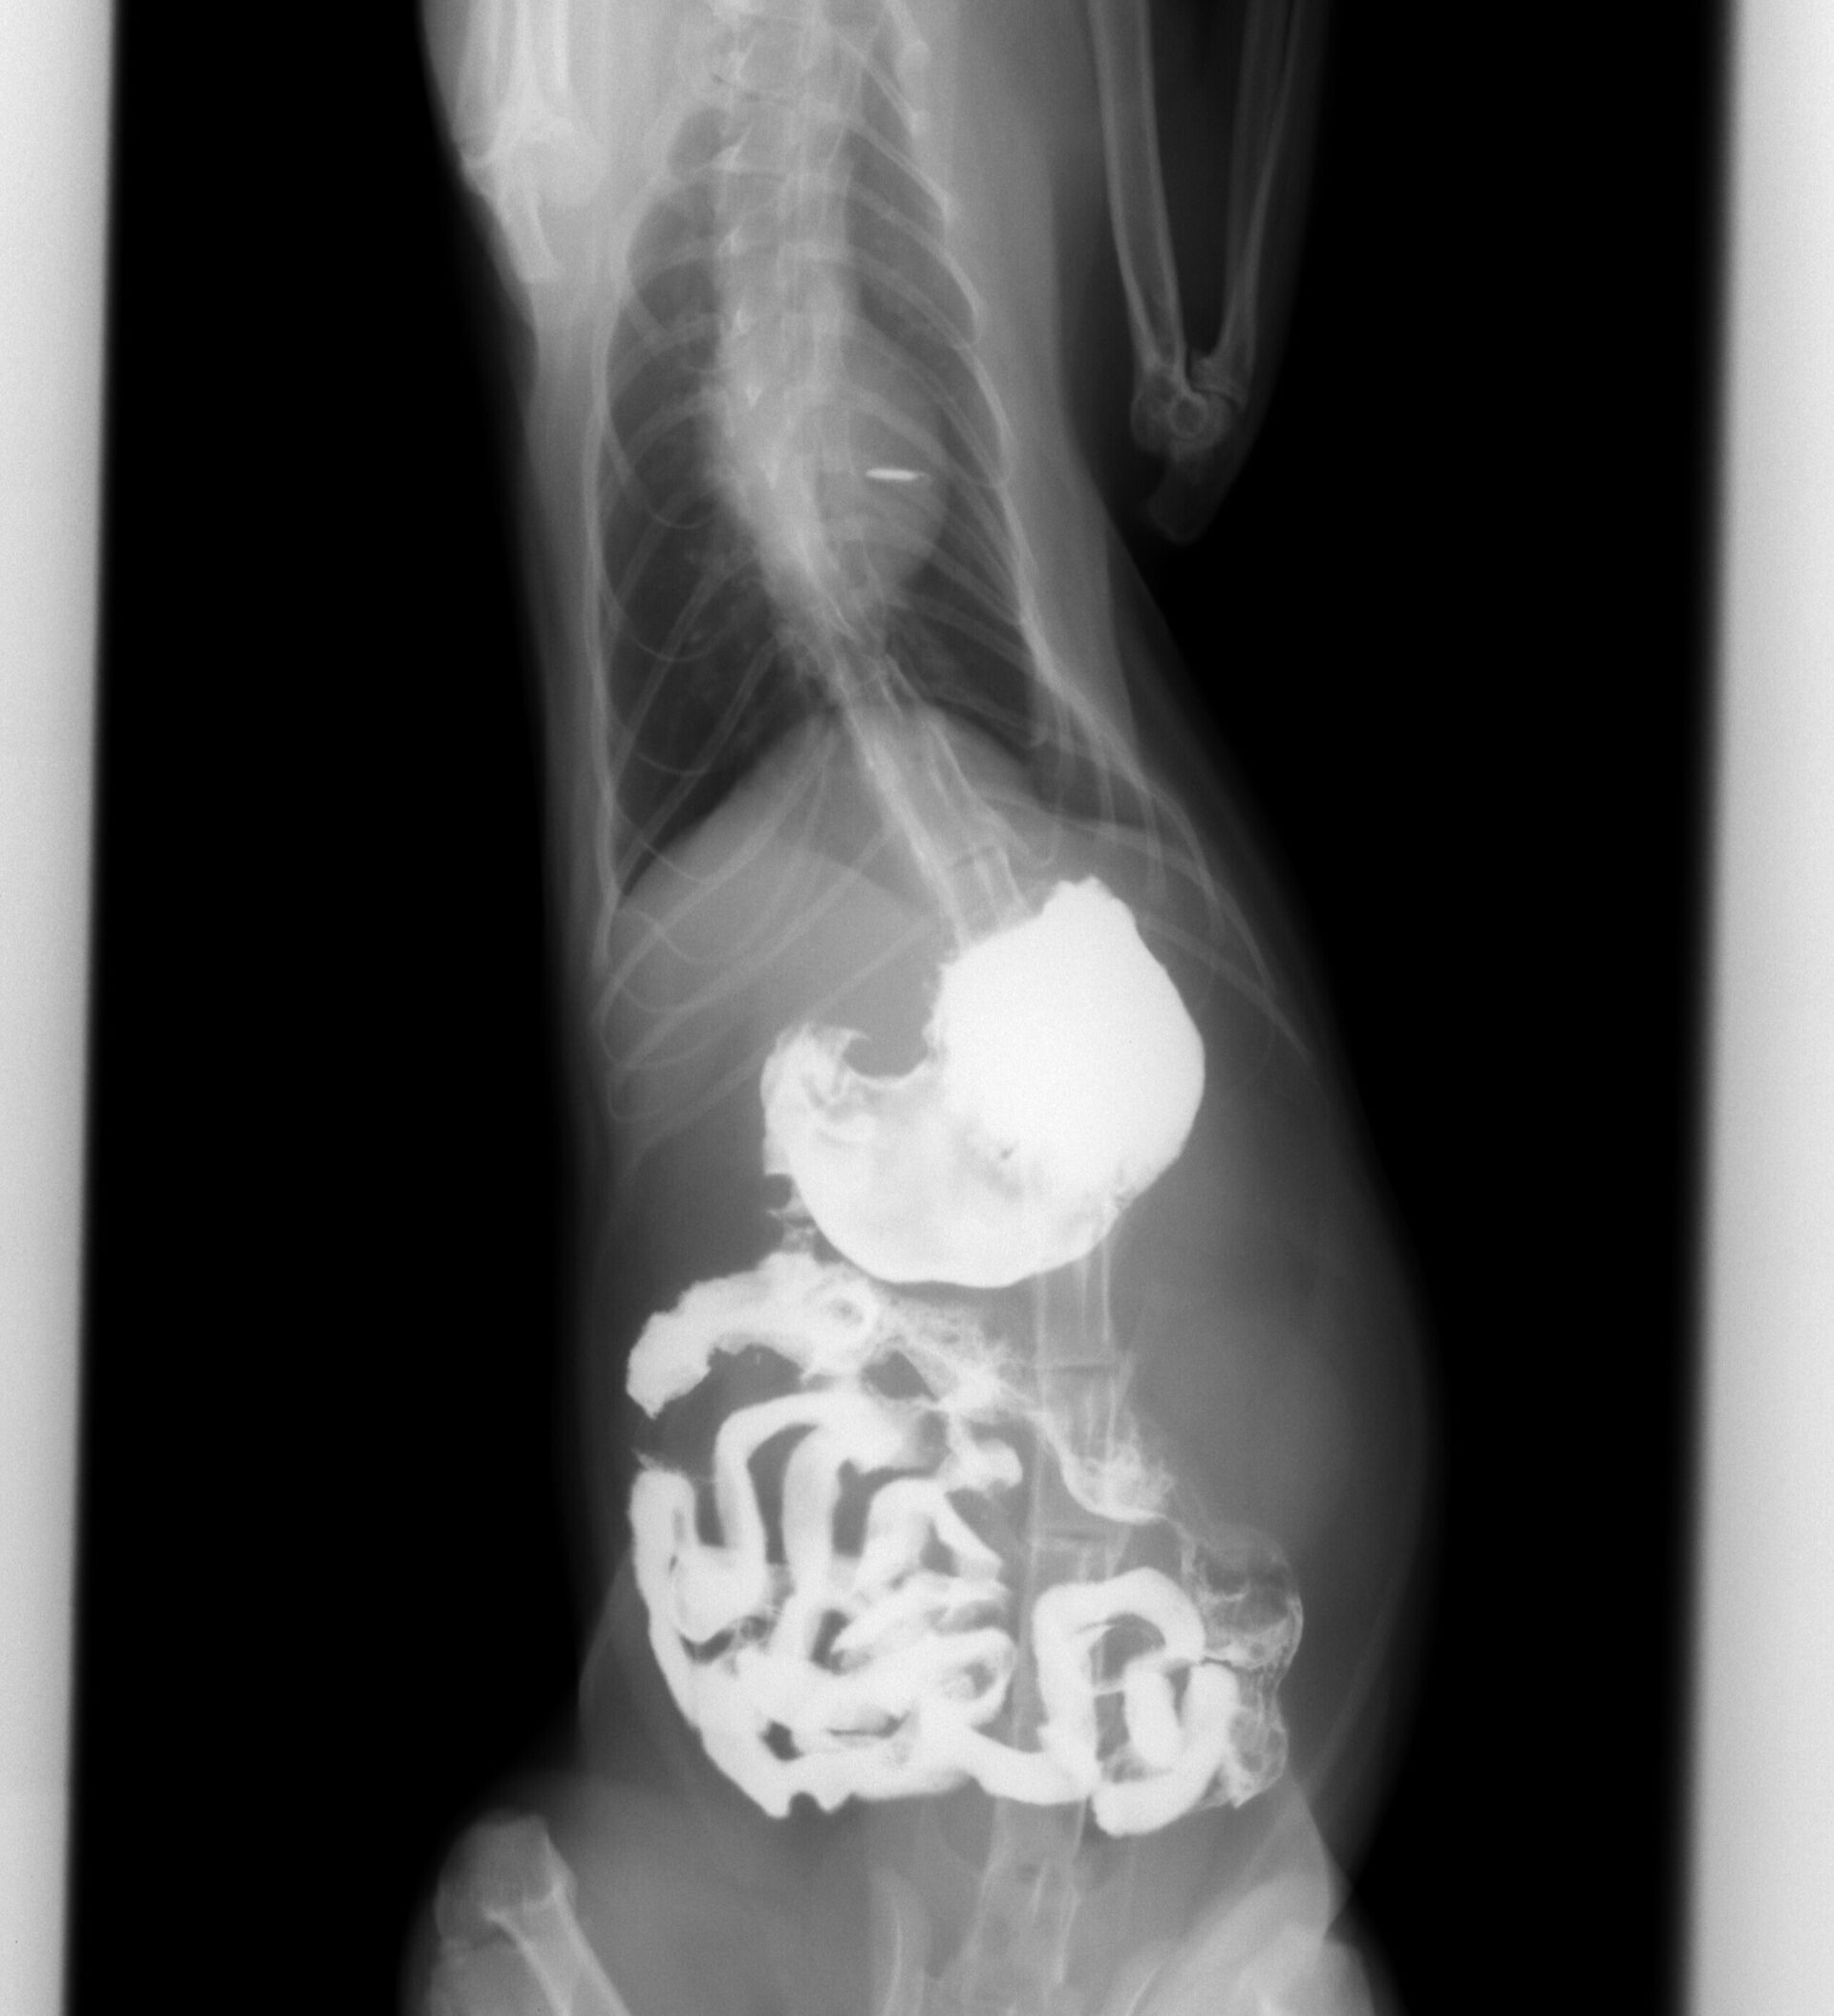

猫の紐状異物の誤嚥についてです。突然、ある日を境に食欲がなくなり、水を飲むたびに嘔吐してしまう、ということで来院されました。お腹を触った時に少し痛がるような仕草をしたので、誤嚥を疑いましたが、飼い主さんは「考えにくい。」ということでした。ですが、口腔内を観察してみますと、奥歯に紐のようなものが絡んでいるのが認められました。紐状異物の誤嚥の可能性が考えられましたので、バリウム検査をしました。その結果が下の写真です。

バリウムを飲ませた直後の写真ですが、矢印で示していますように食道にバリウムが残っています。これは紐状異物が食道にあることを示しています。その後4時間まで撮影しました。その結果が下の写真です。小腸まで達したバリウムは小腸の変形を示しています。これは紐状異物が小腸まで達していることを示しています。